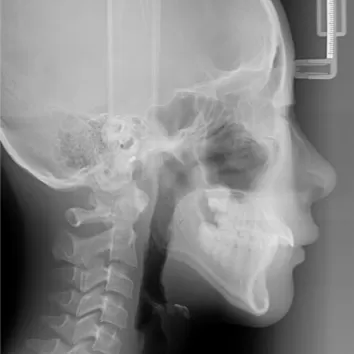

Rayons X avant le traitement

[Radiographie panoramique/Céphalogramme latéral]